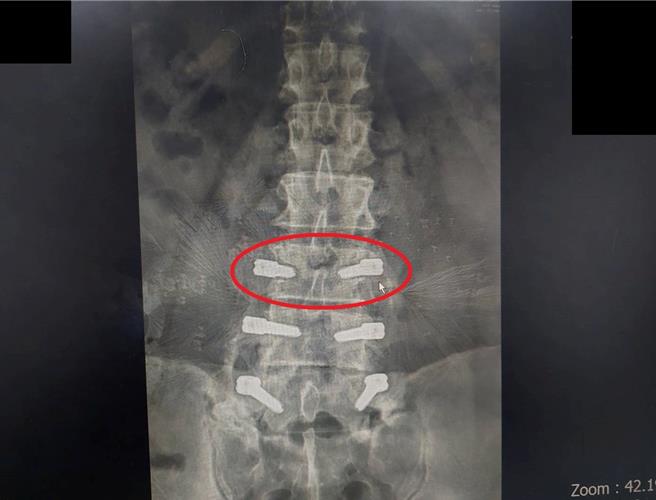

張先生因細菌感染,造成腰椎鋼釘鬆脫(紅圈處)。(大千醫院提供/謝明俊栗傳真)

大千綜合醫院骨科醫師容志雄表示,張先生的白血球指數一直都很高,在有顯影劑的核磁共振檢查下,看到腰椎鋼釘因為感染導致鬆脫,且從鋼釘處往臀部的方向有明顯的顯影,表示細菌感染已從腰椎處延伸到臀部,才會造成膿瘍發生。此種狀況稱為低度感染,是在手術後發生,當身體狀況良好時,白血球有抵抗力壓制住細菌,但當病人狀況變差時,症狀就會開始出來,最明顯的就是細菌在局部的地方侵蝕骨頭,導致出現空腔、鋼釘鬆脫,隨著侵蝕空間越來越大,細菌數量也增多,外溢出來就造成臀部的膿瘍。